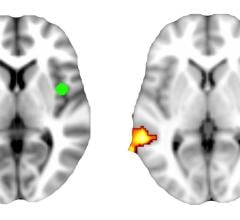

Participating dementia specialists may now enroll patients in the Imaging Dementia—Evidence for Amyloid Scanning (IDEAS) Study at IDEAS-Study.org. Primary care and other doctors not taking part in the IDEAS Study are encouraged to refer eligible patients to participating physicians.